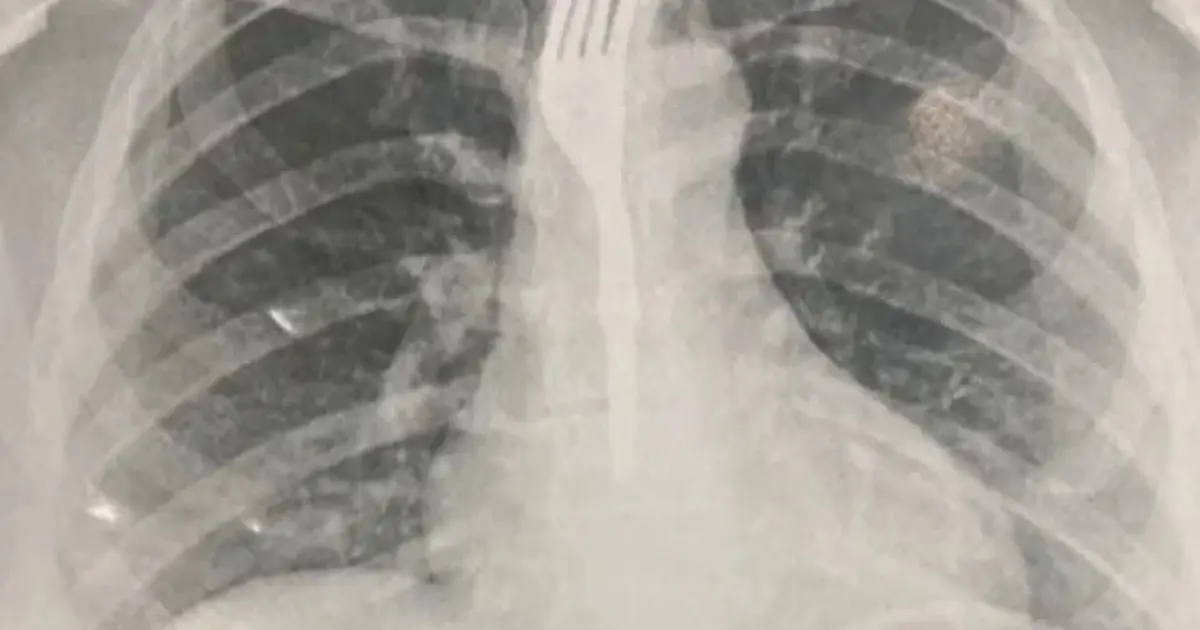

Segundo informações do portal Achei Sudoeste, a paciente — que não teve o nome divulgado — foi levada inicialmente ao Hospital Geral de Guanambi (HGG), onde exames de imagem mostraram que o utensílio estava alojado no esôfago em posição de risco.